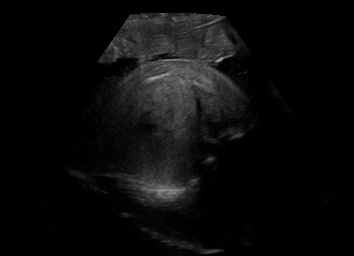

Real in-vivo images. 22 ultrasound sequences were collected using a GE Voluson E8 machine during standard fetal screening exams of 8 patients. Each sequence is several seconds long. We extracted all 4427 frames and resize them to , see Fig. 2 for some examples. The resulting image set was randomly split into training-validation-test sets by a 80-10-10% ratio.